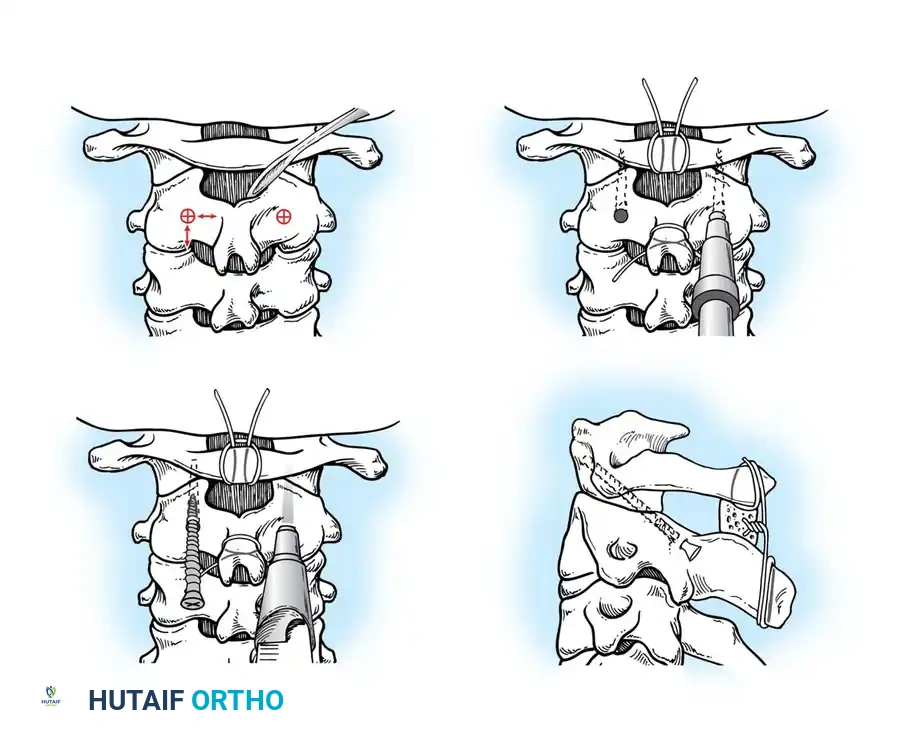

Surgical Steps:

1. Exposure: Retract the longus colli muscles laterally to expose the anterior vertebral bodies and the damaged disc space.

2. Discectomy: Perform a complete discectomy using curettes and pituitary rongeurs. In trauma, the PLL is often torn; carefully remove any extruded disc fragments compressing the cord.

3. Endplate Preparation: Decorticate the cartilaginous endplates using a high-speed burr to expose bleeding subchondral bone, ensuring a robust fusion bed.

4. Grafting: Insert a structural allograft or PEEK cage packed with autograft/demineralized bone matrix (DBM) into the disc space.

5. Plating: Apply a rigid anterior cervical plate. Ensure screws are placed parallel to the endplates and do not breach the adjacent disc spaces.

Fig 6. Anterior cervical plating construct providing rigid stabilization of the anterior column.